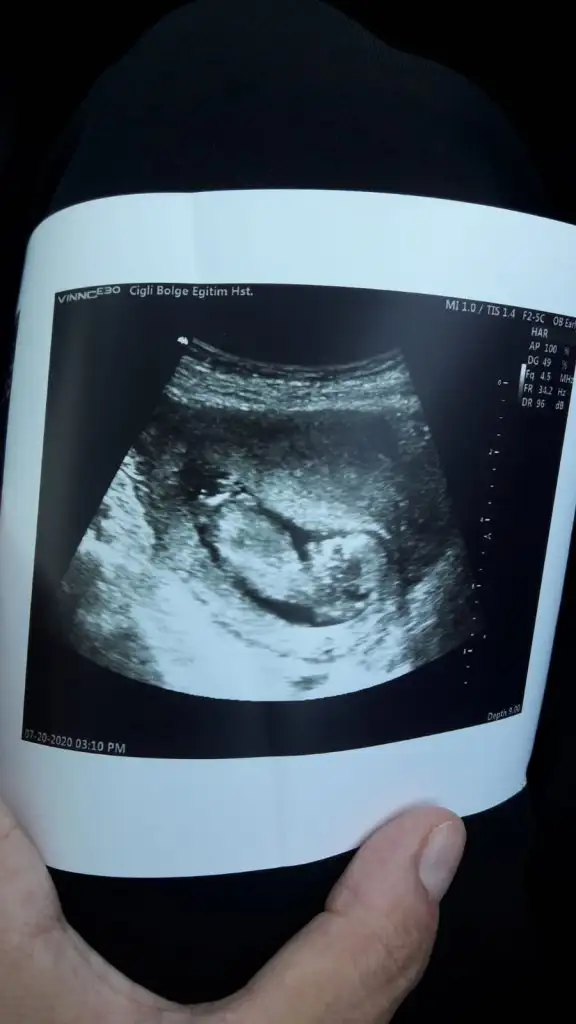

Daha önceki ultrason fotolarından anlayabilirmisiniz yollasam buradan yok göstermiyor bir türlüKaç haftalık sanki erkek gibi geldi başka usg varsa paylaşın az yan pozisyonda minnoş

Kizz11 hafta 1 ama dr 12 hafta 1 gozukmekte dedi tahminde bulunurmusunuz

Kizz :)Bir başka ultrason istemiştiniz bunlar var elimde bacaklarini bağlamışti öylece duruyorduheyecanla yorumunuzu bekliyorumm Ikra meyra

Çok net değil usg ler sanki kız gibi ama emin değilim ☺Bunlar dan belli olurmu acaba biraz ultrason fotolarından şansımız yok ama kısmet artık☺

Kaç haftalık cnm sanki erkek emin olamadım başka usg de paylaş cnm dogum yaptınmı yapmışındır minnoş sen nasılsınızIkracim bu ne acaba yorumlarmisin

Benimki 12+2 atsam bakarmısınız acabaCanım çok net değil emin olamadım sanki sanki erkek olursa 13 hafta paylaş cnm